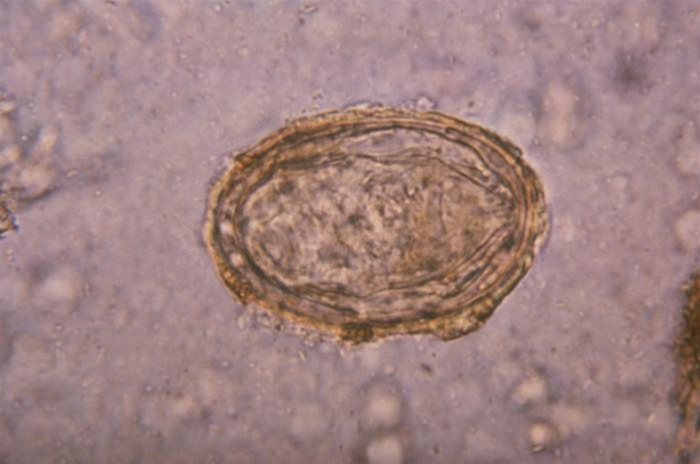

Schistosoma mansoni æg

Schistosoma haematobium æg

Schistosoma japonicum æg